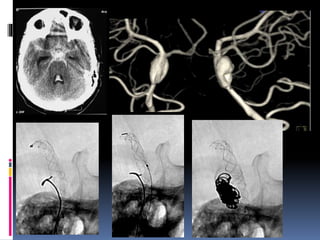

BACKGROUND AND PURPOSE. To learn more about longer term rehab in Fawn Creek KS call our toll-free 247 helpline. Flow diverters rather than endosaccular filling allow endoluminal area inside the blood vessel.

Fourteen 259 of the aneurysms already underwent either open surgery or coiling prior to flow diversion. The deployment of flow-diverter stents may be difficult to analyse on regular DSA. Flow diverters are stent-like devices that are used to treat aneurysms endovascularly.

The purpose of our study was to investigate the clinical. Our data reveal high occlusion rates at 3 and 6 months comparable with those in other flow. Nitinol wire braid with tantalum helix for visibility.

Home Appreciation in Fawn Creek is up 49. The FRED flow diverter is a safe device for the treatment of cerebral aneurysms of various types. Made of solid brass.